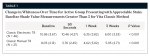

A significant whitening effect was measured for all periods, including the initial 90-second treatment (Table 1 and Figure 2). Multiple comparisons revealed that 1-week and 3-week shade ratings were significantly whiter than baseline and 90-second ratings (P < 0.001) for the electronic ratings (Figure 2). In all other cases, the 90-second, 1-week, and 3-week ratings were significantly whiter than baseline (P ≤ 0.001) (Figure 3).

These data show that statistically significant whitening effects were achieved within the first 90-second treatment. Both evaluation methods showed statistically significant whitening after 1 week (ie, value difference from week one compared to baseline) and also after 3 weeks (ie, difference between baseline and 3-week values).

For the subjective measurement of the Vita Classical Shade Guide, an average whitening effect was determined to be on the order of 1 to 2 for 90 seconds; 3 to 5 for 1 week; and 4 to 6 for 3 weeks of once-daily use. Similarly, data from the Vita Easyshade yielded an average whitening effect on the order of 3 to 4 for 1 week and 4 to 6 for 3 weeks.7,8 The data also indicated a progressively improved whitening effect, suggesting that sequential use may be important for optimizing the whitening results, with maximum whitening occurring within the 1-week and 3-week periods with once-daily use (Figure 4 and Figure 5).